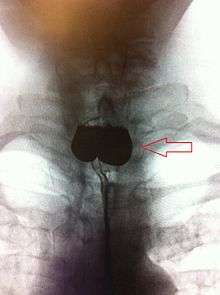

The simple barium swallow will normally reveal the diverticulum. It may also be found with upper GI endoscopy, or CT with oral contrast.